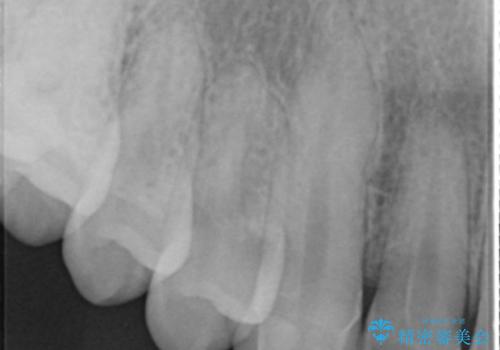

- 「前歯に穴が開いたから診てほしい」とのことで来院。

全体的に歯と歯茎の間境目が白く、右上の前歯は穴が開いてしまっていました。

インレーでの修復はできない場所であるため、セラミッククラウンでの治療になりました。

全体的に歯の脱灰が目立っており、右上の犬歯のみ状態が悪く穴が開いてしまっていました。

審美的にも優れるセラミッククラウンで修復し、他の歯も同じ状態になってしまわないよう歯磨き指導をさせていただきました。